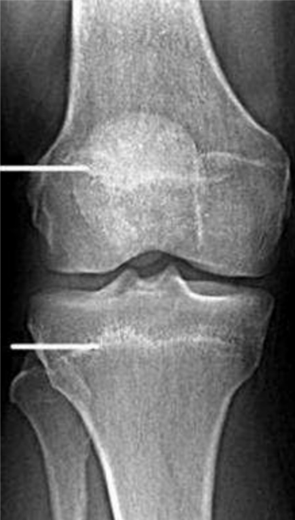

要想回答这些问题,我们就要从人是怎么长高的说起。人体的长高是肌肉、骨骼等共同生长的表现,其中以骨骼生长最为关键。在未成年人的骨骼X线片中,我们可以发现骨的两端存在着非常特殊的区域——骨骺和生长板,骨骼的变长就是通过这一区域的生长来实现的。同时,随着年龄的增长,骨骺的生长逐渐缓慢,生长板逐渐变薄,最终完全与骨骺融合,骨就不能再生长,人也就不能继续长高。所以,在医学上,我们人类有两个年龄,一个是实际的年龄,另一个就是骨龄。孩子最终的身高是由骨龄决定,而不是年龄决定的。

接下来,我们一起看两张骨龄片。大家先看左边这张,在关节之间可以清晰地看到软骨层和缝隙,在手掌下端,这些小骨头之间的缝隙并没有完全融合,这说明骨骺还没有完全融合,还具有生长潜力。大家再看右边这张,关节之间的软骨层没有了,缝隙变得很紧密,手掌下方小骨头之间的缝隙完全融合,这说明骨骺已经完全融合,已经没有任何生长潜力了。通过这样的比较,相信大家了解了一个道理:骨骺一旦融合,是没有任何长高的空间了。